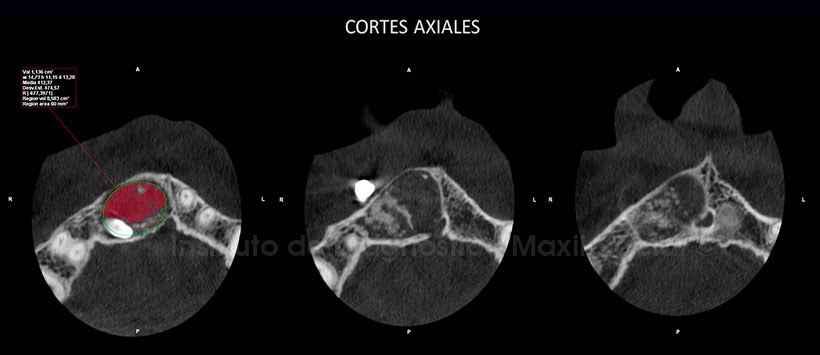

A la evaluación tomográfica, evidenciamos en los cortes axiales la presencia de una lesión mixta ubicada en la zona anterior del maxilar superior, la cual condiciona el desplazamiento de ambas tablas óseas a predominio de la tabla vestibular. Asimismo, esta entidad está asociada al diente supernumerario previamente descrito y de un volumen aproximado de 1,136 cm3. (Figura 2)